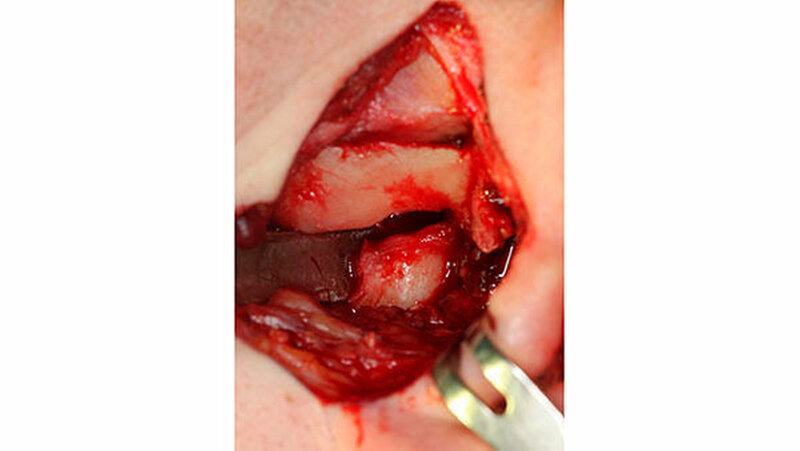

Therapie: Kiefergelenkersatz mit Endoprothesen

Mit der virtuellen Planung, individuellen Kiefergelenkprothesen und einer zusätzlichen Rückpositionierung des Oberkiefers in die ursprüngliche Lage erfolgte dann die Operation. Alles erfolgte in einem Operationsgang. Die Bonner MKG-Chirurgen fertigten die Endoprothesen für die Frau individuell im CAD-/CAM-Verfahren an. Dafür wurden die Daten der Computertomografie des Schädels zugrunde gelegt.

Durch diese hoch anspruchsvollen Verfahren ließ sich annähernd die ursprüngliche Position des Unterkiefers vor der Einschmelzung wiederherstellen; in der gleichen Operation wurde die Position des Oberkiefers der jetzt idealen Stellung des Unterkiefers angepasst.